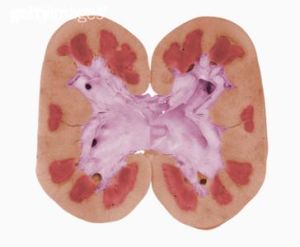

2.與急性腎衰的鑑別 CRF與急性腎衰的鑑別,多數情況下並不困難,有時根據患者的病史即可作出鑑別診斷。在根據患者的病史對急、慢性腎衰竭鑑別困難時,可考慮從以下幾方面作出鑑別:根據影像學檢查(如B超,CT等)結果進行分析如雙腎明顯縮小,則支持CRF健康的診斷;根據腎圖檢查結果進行分析;如果患者訴說的腎衰竭病史少於1個月,而無明顯貧血,則支持急性腎衰竭的診斷;如貧血明顯,而近期無急性出血病史,則支持CRF的診斷;根據指甲肌酐的水平進行鑑別診斷,也有一定參考意義,據北京醫科大學第一醫院報導,指甲肌酐水平可反映患者3~4個月前的血肌酐水平,如指甲肌酐的水平高於正常,則支持CRF的診斷;如指甲肌酐的水平不高於正常,則支持急性腎衰竭的診斷。